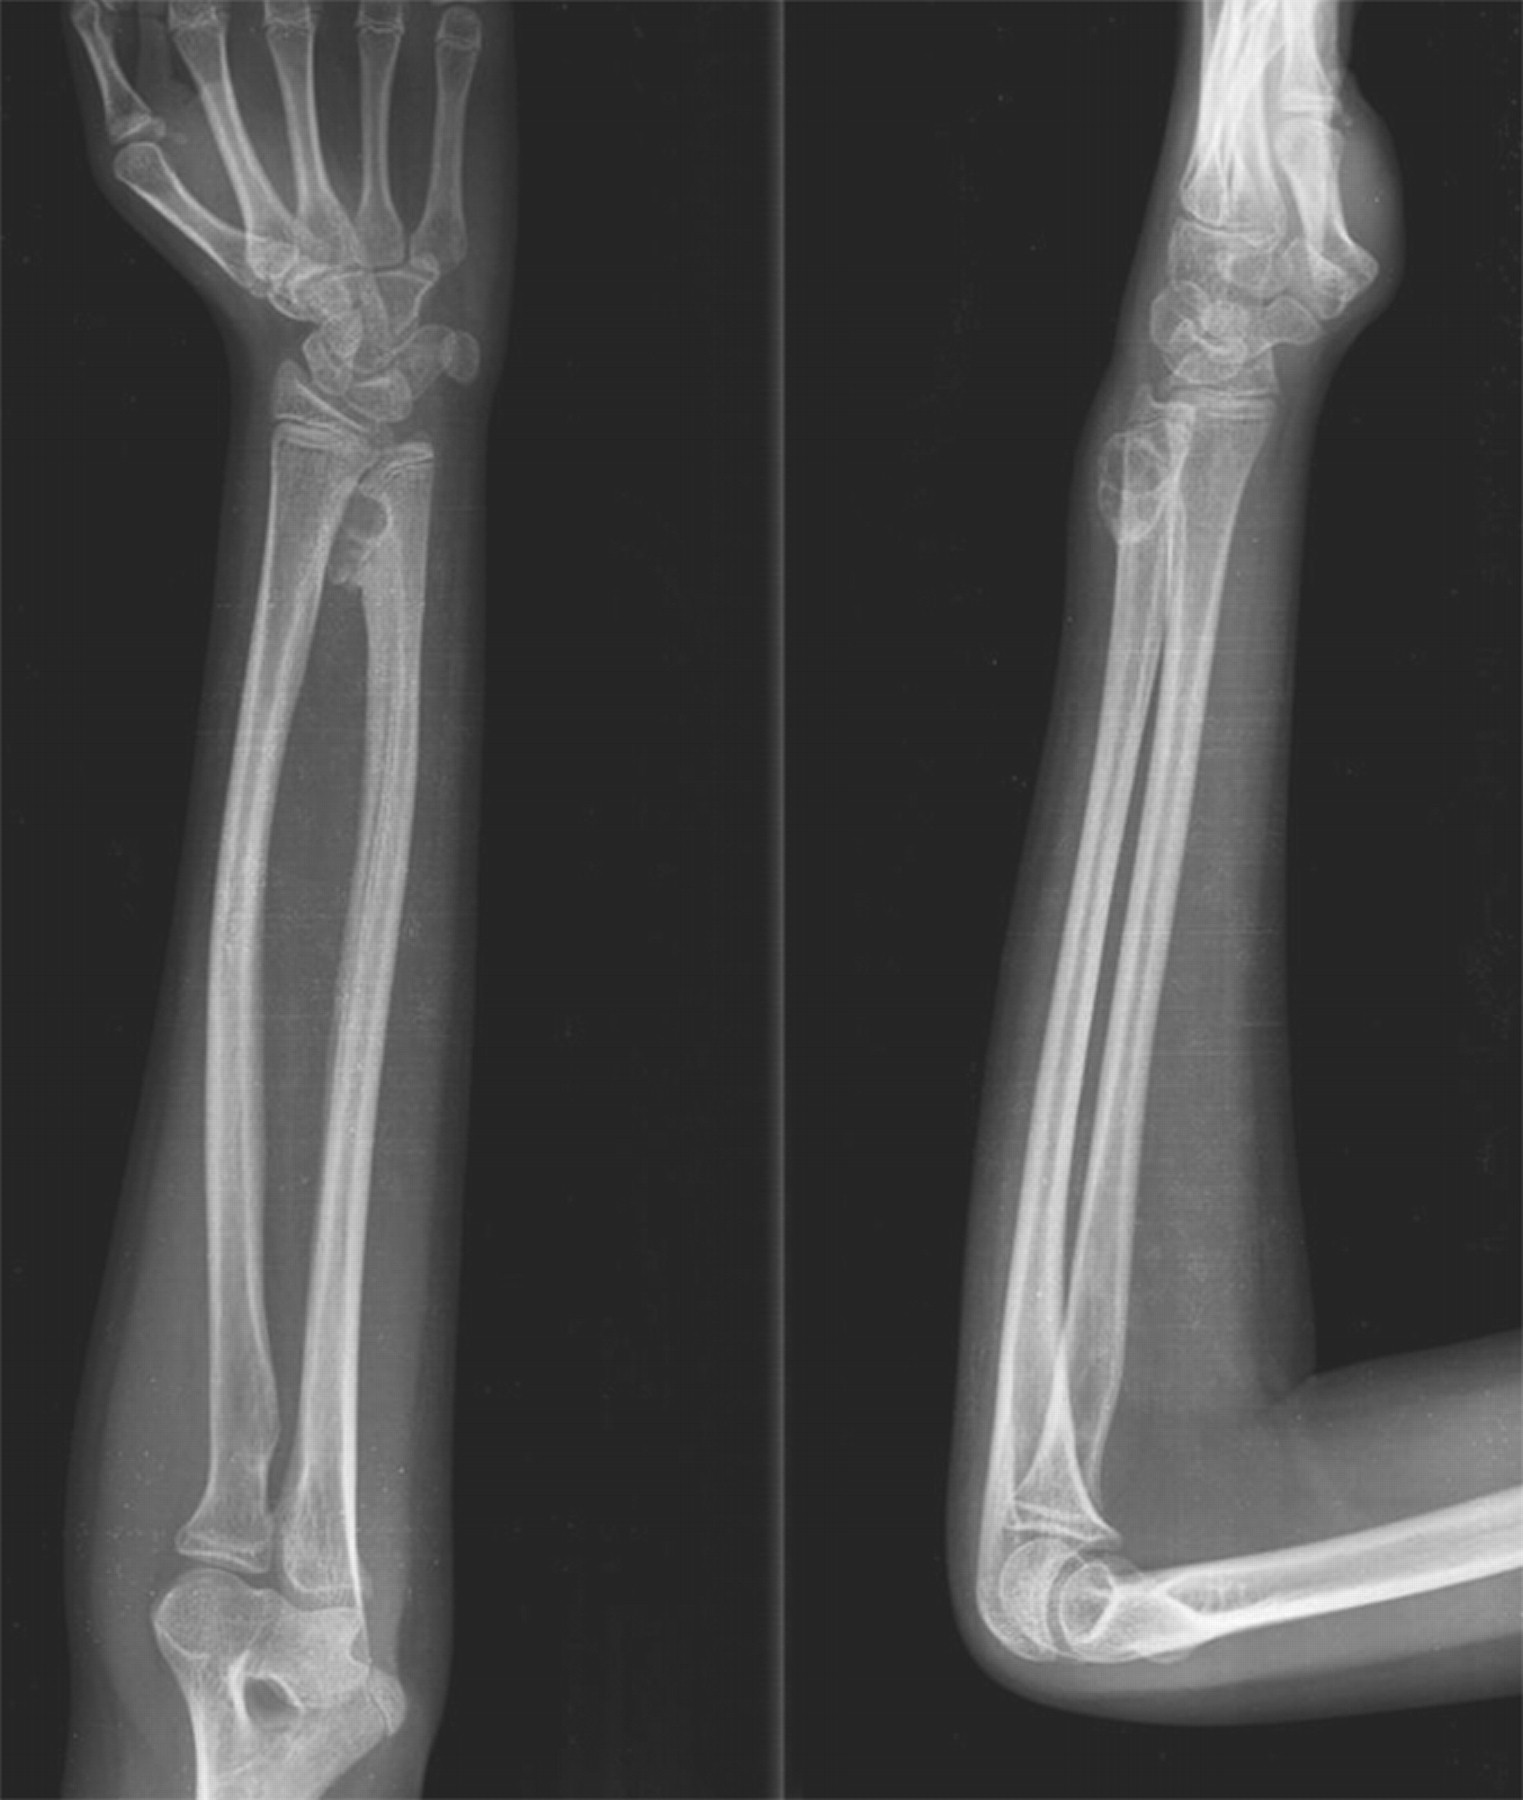

From boneandjoint.org.uk

Florid reactive periostitis of the forearm bones in a child Bone & Joint Symptoms Of Periostitis Learn about the types, diagnosis and treatment of. Periostitis is a condition characterized by inflammation of the periosteum around tubular bones and in the tibia, known as shin splints or. Periostitis, or shin splints, is inflammation of the membrane that envelops the shinbone, often affecting runners. Periostitis is a painful condition characterized by inflammation of the periosteum, the connective tissue. Symptoms Of Periostitis.